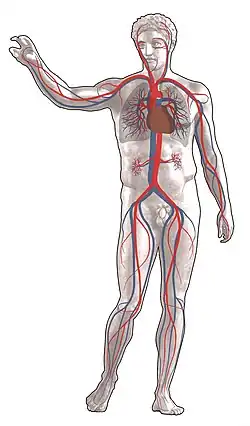

The human circulatory system. Red indicates oxygenated blood, blue indicates deoxygenated. | |